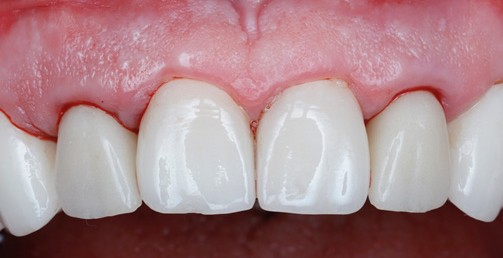

The 6 weeks follow up showed stable soft tissue, no signs of inflammation, and good maintenance by the patient. The implants showed no mobility and appeared to be integrating uneventfully.